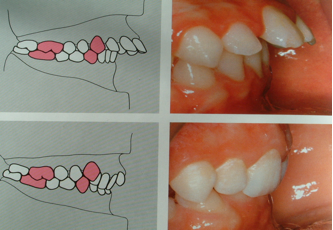

- Alterazioni sul piano sagittale

Si intendono tutte quelle alterazioni in cui un’arcata è troppo avanzata o troppo arretrata rispetto all’altra. Esse vengono classificate in tre classi ortodontiche:

- 1°classe: rapporti antero-posteriori normali

- 2°classe: arcata superiore avanzata rispetto l’inferiore (superiore troppo avanti e/o inferiore troppo indietro )

- 3°classe: arcata superiore arretrata rispetto l’inferiore (superiore troppo indietro e/o inferiore troppo avanti )

Le tre classi ortodontiche posso essere :

-Dentali ovvero legate ai rapporti intercuspidali,classificati secondo Agle.

-Scheletriche ovvero legate ai rapporti tra mascellari secondo misurazioni effettuate sulla radiografia laterale del cranio (teleradiografia ).

La classificazione di Angle prende in considerazione il rapporti del primo molare dei canini

I classe – il primo molare superiore e/o il canino superiore risulta

arretrato di mezza cuspide rispetto al corrispondente inferiore.

II classe – il primo molare superiore e/o il canino superiore risulta avanzato di almeno mezza cuspide rispetto al corrispondente inferiore.

III classe – il primo molare superiore e/o il canino superiore risulta arretrato di almeno mezza cuspide rispetto al corrispondente inferiore.

1^ classe dentale

2^ classe dentale

3^ classe dentale

Nella II classe basale avremo: retrusione della mandibola rispetto alla mascella (corrispondente a dislocazione posteriore alta dei condili rispetto alle fosse temporali con conseguenti traiettorie condilari più ripide), lingua interposta anteriormente a riposo e in deglutizione, sigillo labiale inefficiente in quanto il labbro inferiore risulta posteriorizzato rispetto al superiore. Tale situazione si ripercuote sulla postura cervicale e di conseguenza sulla postura in generale. Si potrà, ad esempio, avere prevalenza del tono muscolare posteriore, estensione dell'occipite rispetto all'atlante (la testa "si apre" sul collo), tratto cervicale in rettilinizzazione ma con concentrazione dell'iperlordosi nel segmento atlante-occipite.

Nella III classe avremo: protrusione della mandibola rispetto al mascella (condili in posizione anteriore e inferiore e quindi traiettorie condilari più dolci), lingua in posizione bassa con appoggio sulla mandibola con conseguente incompetenza del sigillo labiale in quanto, in questo caso, il labbro inferiore risulta anteriorizzato rispetto al superiore. In base alle reazioni individuali si potrà, ad esempio, avere una prevalenza della muscolatura anteriore del collo, occipite in flessione rispetto all'atlante (la testa "si ripiega" verso il petto "chiudendosi" sul collo), con alterazione della fisiologica lordosi cervicale che tende a concentrasi nel tratto inferiore per poi rettilinizzarsi o, addirittura, invertirsi nel tratto superiore.